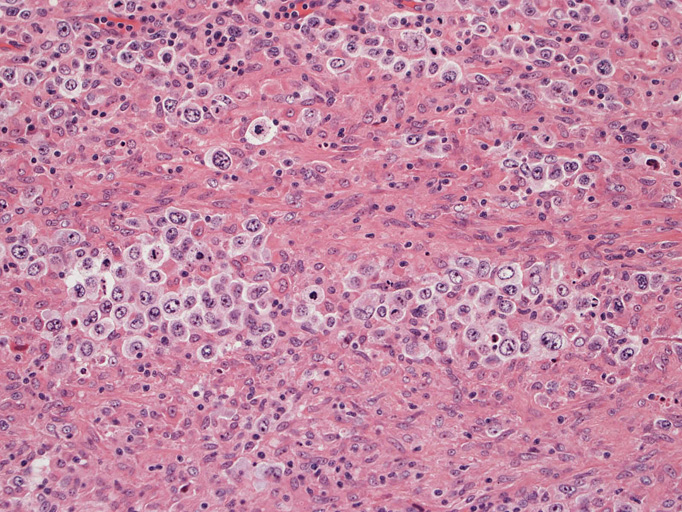

病理組織所見†

頸部リンパ節病理組織所見

直径17mmの腫大したリンパ節。被膜は軽度線維性肥厚を示す。リンパ節の基本構造は失われ不明瞭な結節様構造が集蔟しているように見える。

光顕および免疫染色所見

結節構造内では, 好酸性細胞質をもつ組織球の増生を背景に大型異型細胞が散在性または集蔟して増殖している。被膜下にも線維化組織内にbizzarreな大型細胞が認められる。リンパ球は小型リンパ球が大型異型細胞を含む組織球性の結節辺縁に存在する。大型細胞は, centroblastic cellが多く, その他 Hodgkin cell-like cell, RS細胞様巨細胞, 腎臓型の核をもった細胞, 多型核の細胞など多彩な形態を示す。異型核分裂像をふくむ核分裂像が多い。